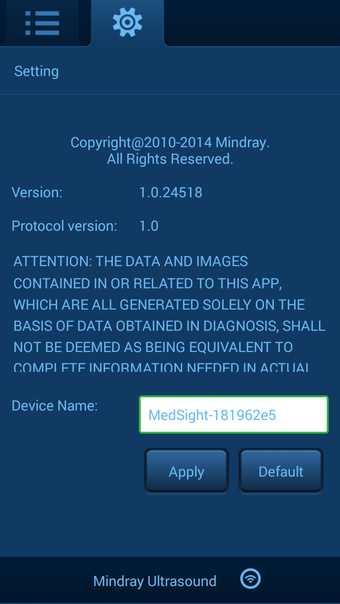

Uygulama birkaç faydalı özellikle birlikte gelir. İlk olarak, kullanıcılar ultrason sistemine kaydedilen hasta bilgilerini uzaktan inceleyebilir ve hasta verilerini indirebilir. İkinci olarak, kullanıcılar hasta verilerinin indirme ilerlemesini ve durumunu kontrol edebilir. Üçüncü olarak, kullanıcılar ultrason görüntüleri ve sine döngüleri de dahil olmak üzere hasta verilerini yerel olarak gözden geçirebilir. Son olarak, uygulama temel ayarlama fonksiyonları ve yazılım bilgileri sağlar. Uygulama kullanımı kolaydır ve hastaların akıllı cihazlarında ultrason görüntülerine ve sine döngülerine erişmeleri için pratik bir yol sunar.